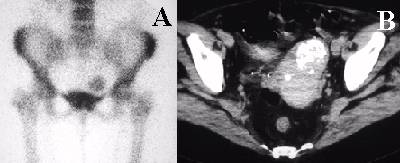

Anterior image of the pelvis from a bone scan shows increased uptake in the soft tissues above the bladder.

Diagnosis

Uterine fibroid